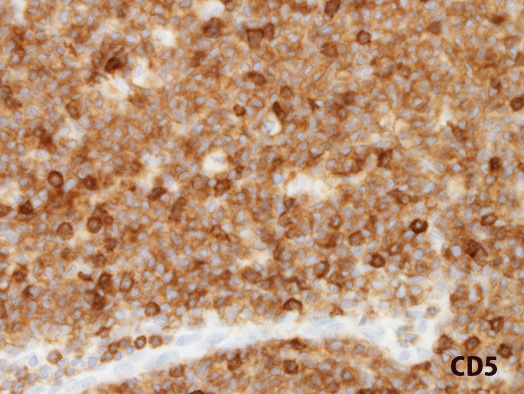

免疫染色:増殖リンパ球はCD20, CD5陽性。核にcyclin D1陽性

CD5; 標本がやや厚切り切片。当院の染色ではMCL細胞は乏しい細胞質に染まる。教科書のようにきれいに細胞膜には染まらなかった。賦活の前処置のためかもしれない。混在するCD5+T細胞がより強く染まっている。